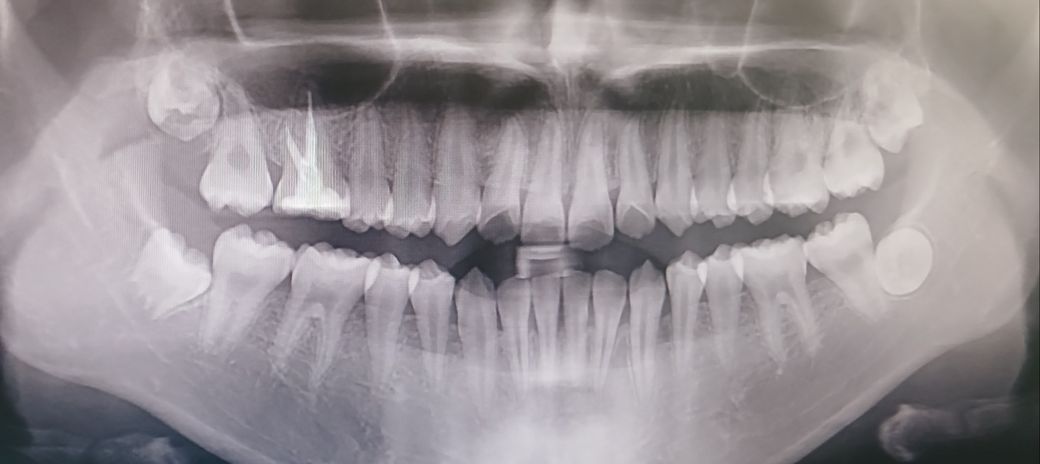

16번 어금니 신경치료, 발치 후 사랑니 교정 가능할까요?

제가 16번 어금니 충치때매 신경치료를 하고 크라운을 씌운 상태입니다. 그치만 언제까지고 크라운을 계속 사용할 수 없는 노릇이고, 제가 사랑니가 있는 것 같아서 만약에 몇 년 뒤 발치 후에 사랑니 교정? 이런 걸 통해 빈 곳을 매꿔서 자연 치아로 사용할 슈 있을까요? 엑스레이 찍은 거 보면 사랑니가 있는 것 같은데..... 참고로 현재 19살입니다

• 1번 째 사진

• 신경치료를 하고 나서도 이상이 없다면 계속 사용해도 됩니다. 특별히 문제가 없다면 지금 상태에서 유지하시면 됩니다. 사랑니를 이용하여 어금니를 대체하는 것은 학문적인 관점에서 시행하고 있으나 보편적으로 행해지는 술식도 아니며 예외적인 몇 몇 케이스에서만 가능하므로 현재 말씀하신 부분이 가능한지는 치과 방문 후 검사를 해보아야 합니다.

1. 신경치료 후 크라운을 씌웠다면 크라운은 보통 5~10년 정도 사용하며 관리만 잘 된다면 좀 더 오래 쓸 수도 있습니다.

2. 나중에 해당 치아를 뽑아야 할 때 사랑니가 이를 대체하는 경우는 자기치아이식술에 해당되는데 사랑니가 멀쩡한 상태여야 하고, 수월하게 뺄 수 있어야 시도해볼 수 있는 등 조건이 다소 까다롭긴 합니다.

3. 일단은 지금으로서는 그런 거에 대한 고민보다는 크라운 씌운 치아에 대해 잘 관리해주는 것이 우선입니다.